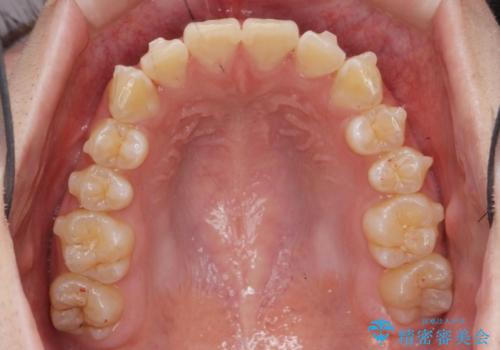

がたつきが無くなり満足して頂けました。

矯正が終わった後は保定装置を使用しないと後戻りしてしまうのでしっかりと保定装置を使用する必要があります。